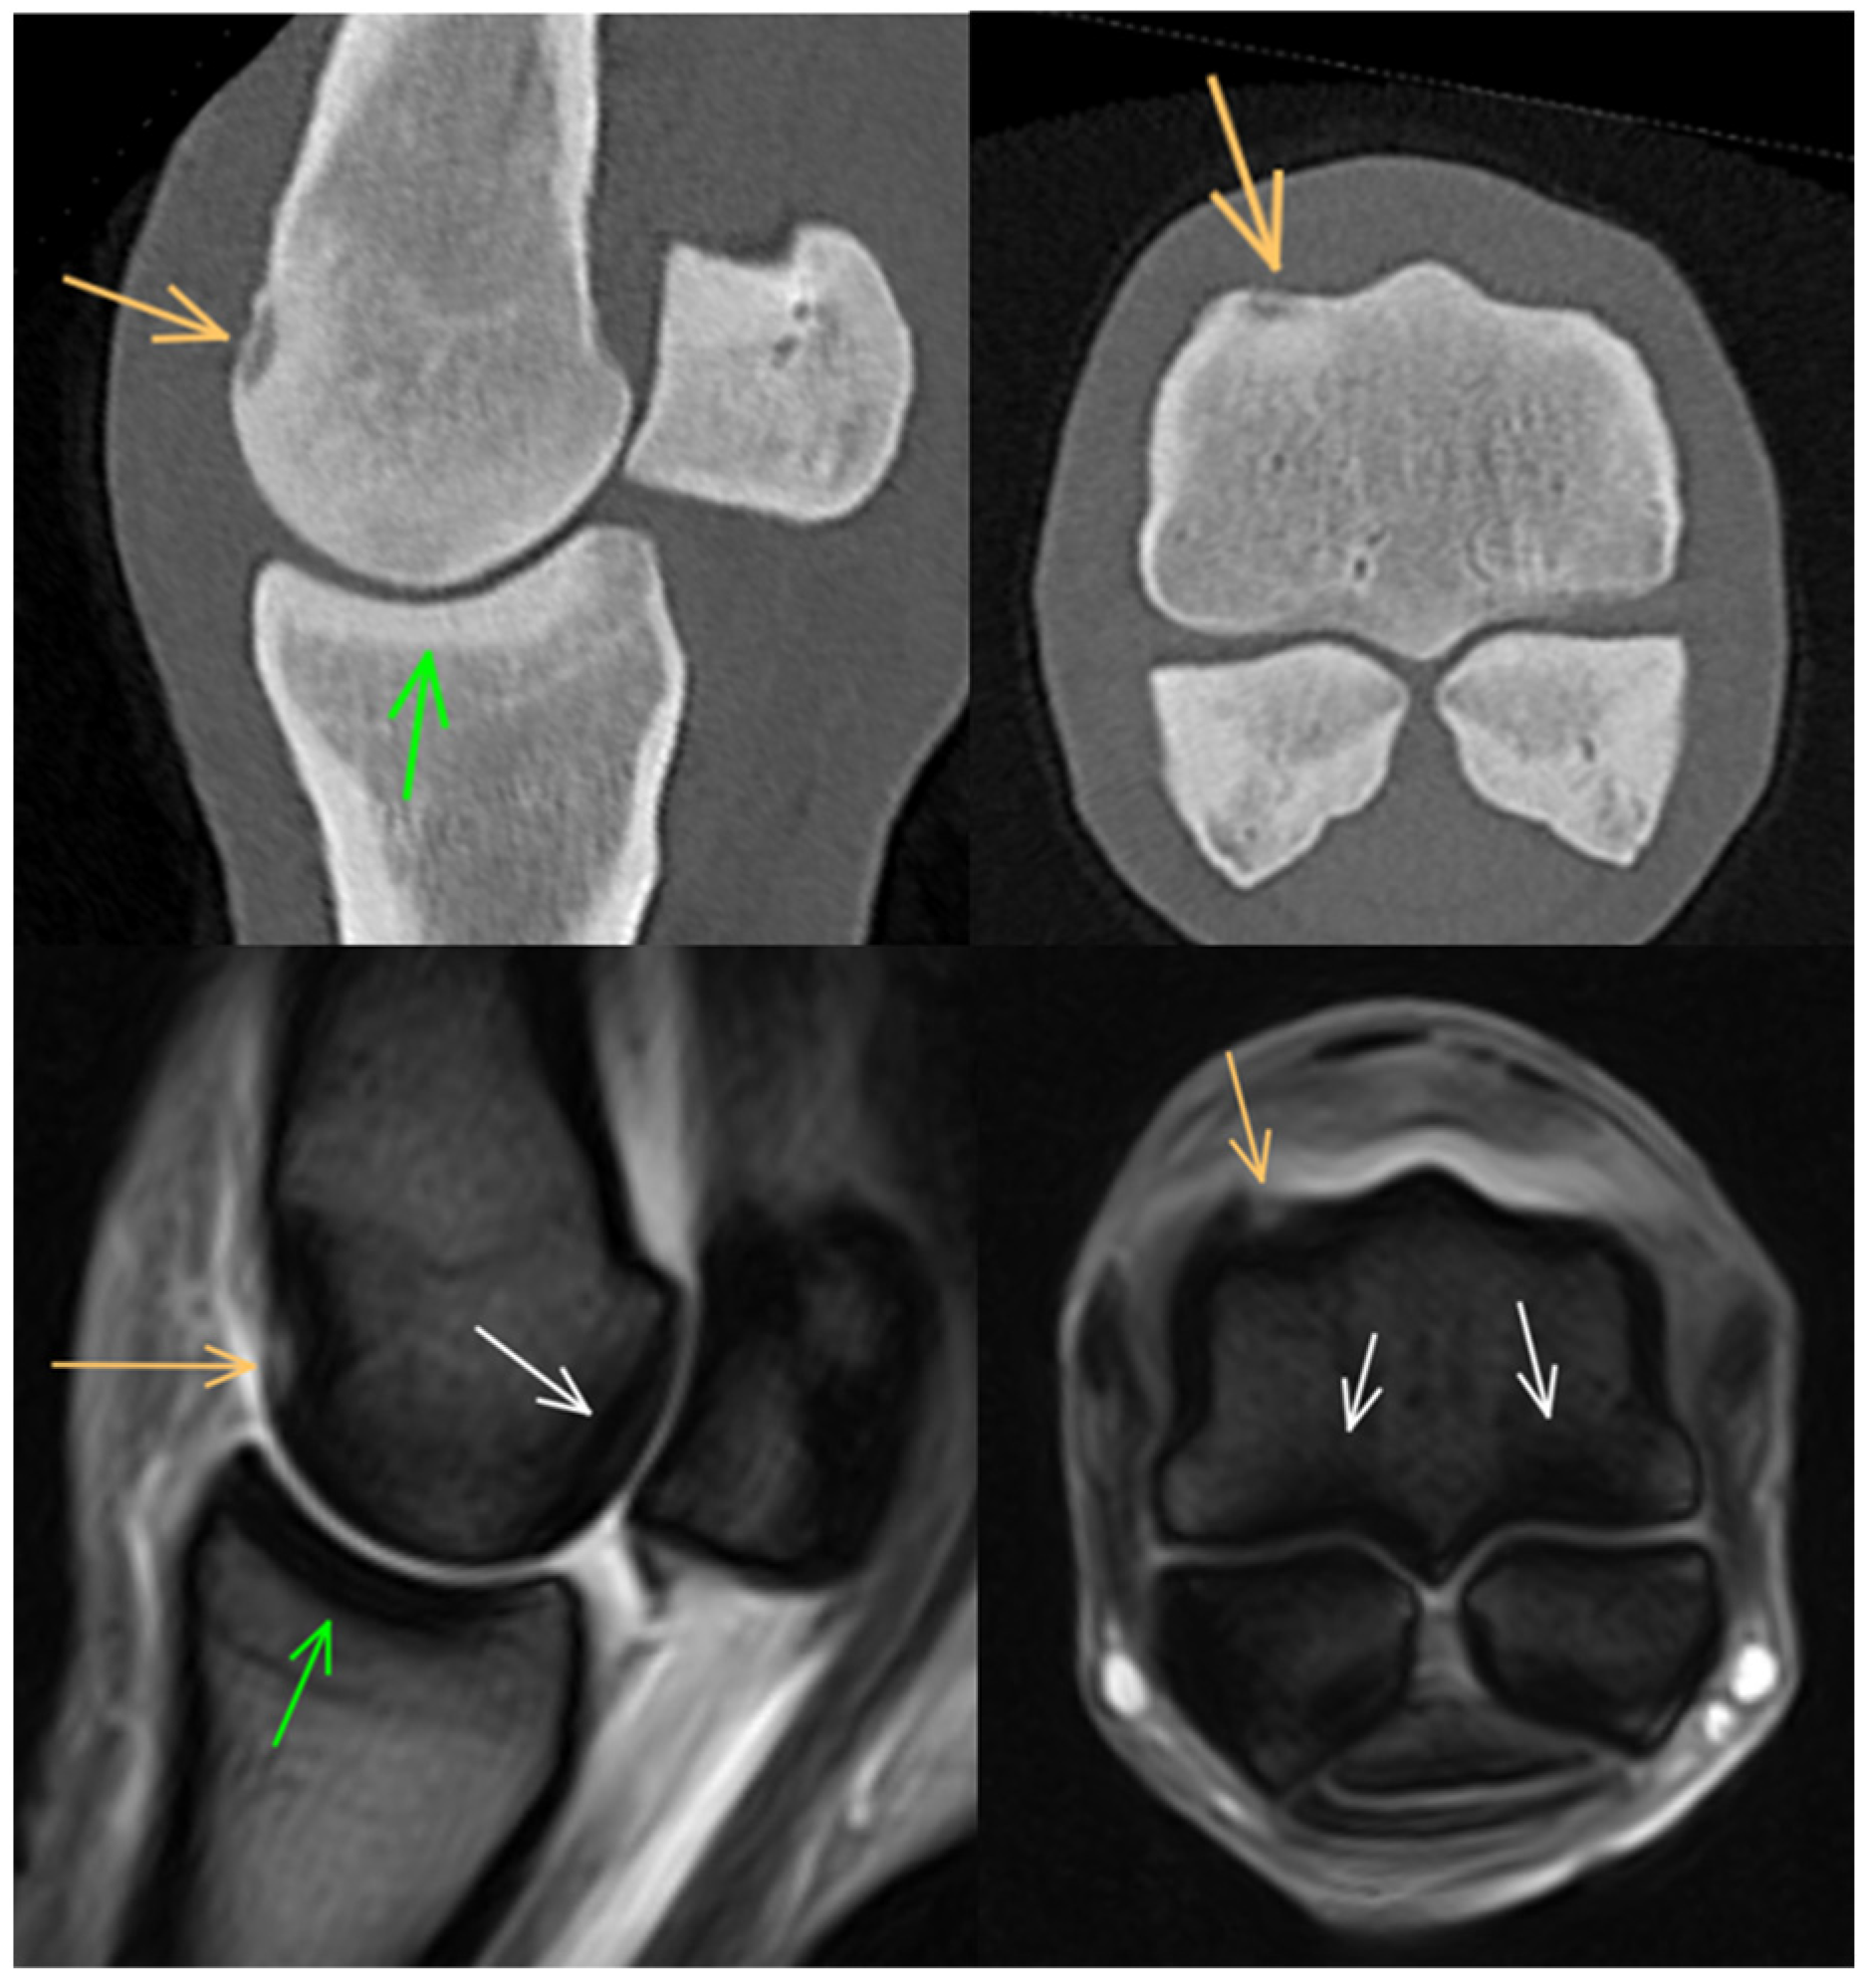

3.3. Proximal Sesamoid Bones

3.4. Soft Tissues